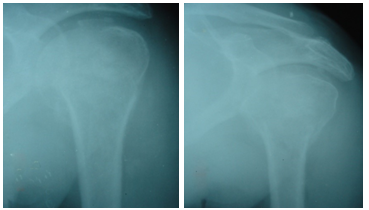

Figure 10 The patient with post traumatic avascular necrosis of femoral head – There was collapse of humeral head along with poor shoulder function.

The interval between injury and surgery was around 4.5 (range 0-9) days; 33 (84.61%) patients were operated in a weeks’ time. The duration of external fixation removal was 48 (range, 39-56) days. The time to radiological union took almost 12 (range 9-14) weeks. The follow-up period was 14 months (range, 12-18). Reduction was good and maintained (Almost anatomical reposition of fragments) in 22 (56.41%) patients and fair in 17 (43.58%) patients with a reasonable alignment of opposing fracture fragments. 7 (17.94%) patients had pin tract infections during course of external fixator application and were managed appropriately till healing. 2 (5.12%) patients developed avascular necrosis of head of humerus starting after 6 months of injury. The function of shoulder was done according to the Shoulder Constant Score (C Constant and Murley). The shoulder function was found excellent in 16 (41.02%) patients, good in 14 (35.89%), moderate in 5 (12.82%) and poor in 4 (10.25%) patients. One (2.56%) patient had early inferior subluxation of gleno humeral joint which required frame readjustment despite initial good reduction. This was probably due to complex nature of the four part fracture dislocation (Figure 10).